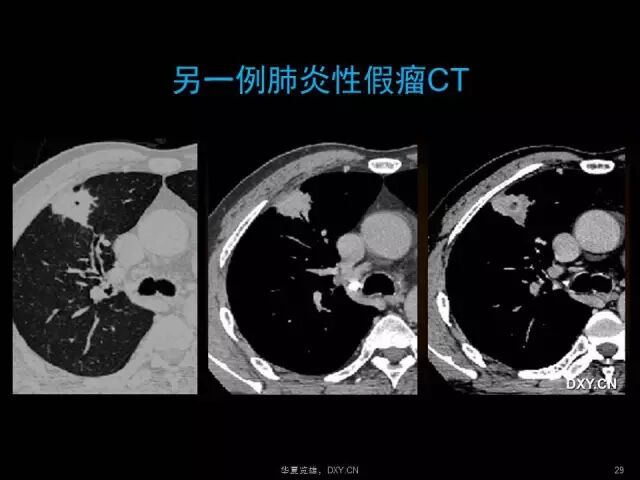

肺炎、肺癌、肺结核在影像学上的征象往往千变万化。